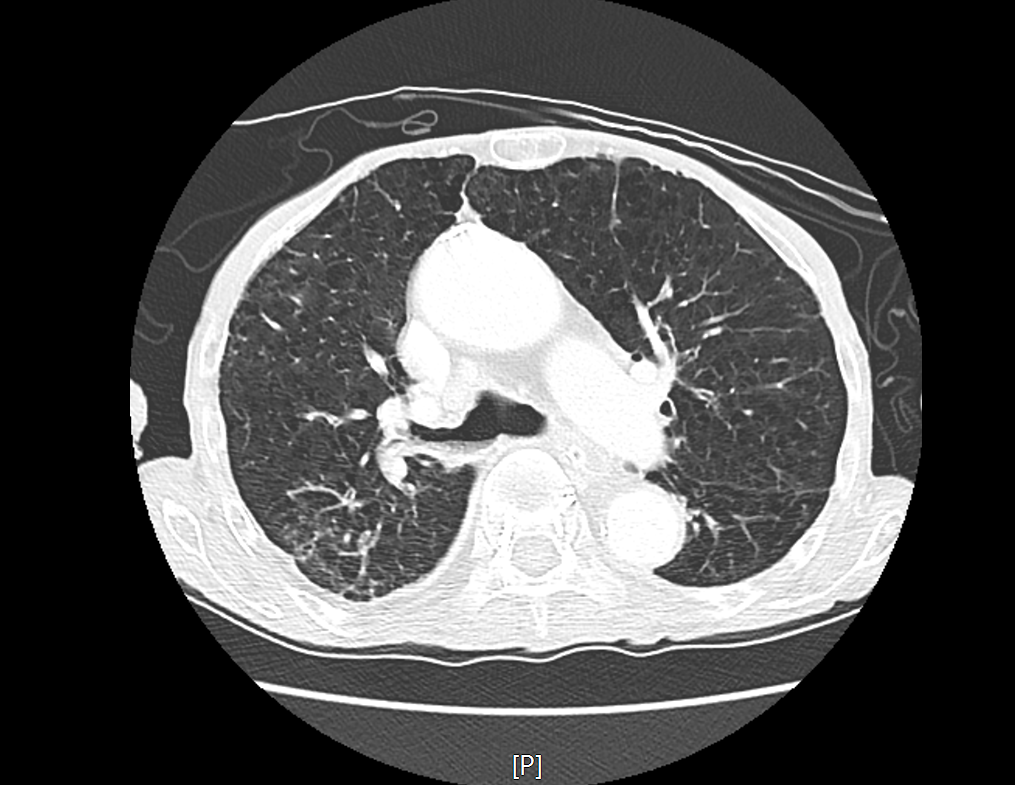

환자의 CT영상을 보시겠습니다.

위 CT영상을 보시면, 환자의 우측 기관지부터 공기 대신 음식물이 들어가 있는 모습을 볼 수있고, 그로 인해 폐실질에는 폐렴과 무기폐가 발생되어 있는 상황이었습니다.

이는 요양원에서 오는 환자분들에게서 흔히 보이는 폐렴의 형태로 흡인성 폐렴으로 생각할 수 있습니다.